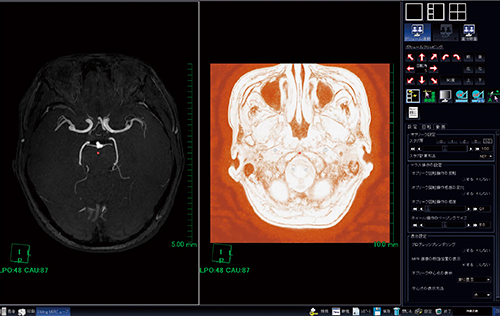

(2)「カラーマップ/WL設定」から「表示」を選択し,VRを表示する(図3)。

図3 「カラーマップ/WL設定」から「表示」を選択